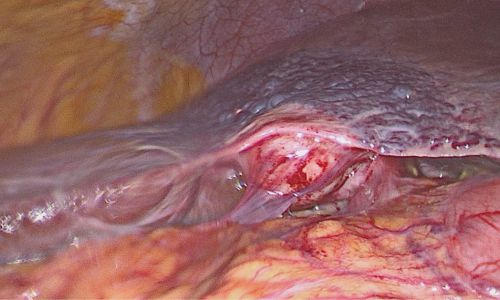

Laparoskopische Cholezystektomie für symptomatische Cholezystolithiasis (CCL) bei „Kasabach-Merritt-Syndrom“ (KMS)